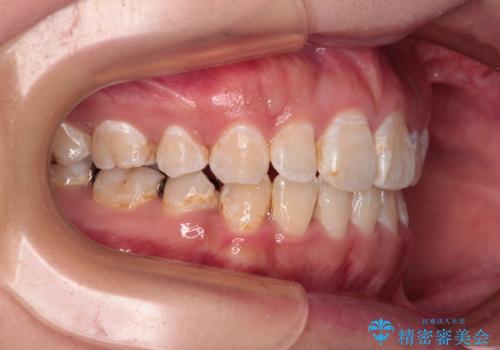

- 前歯のクロスバイトと、口元が閉じにくいとのことで来院された患者様です。

口元の突出感を改善する必要があるため、上下左右の第1小臼歯4本を抜歯し、ワイヤー装置にて矯正治療を行うこととしました。

むし歯のリスクが高かったため、治療が長期化しないように心がけました。

当初の予定通り、2年強で無事に治療を終えることができました。